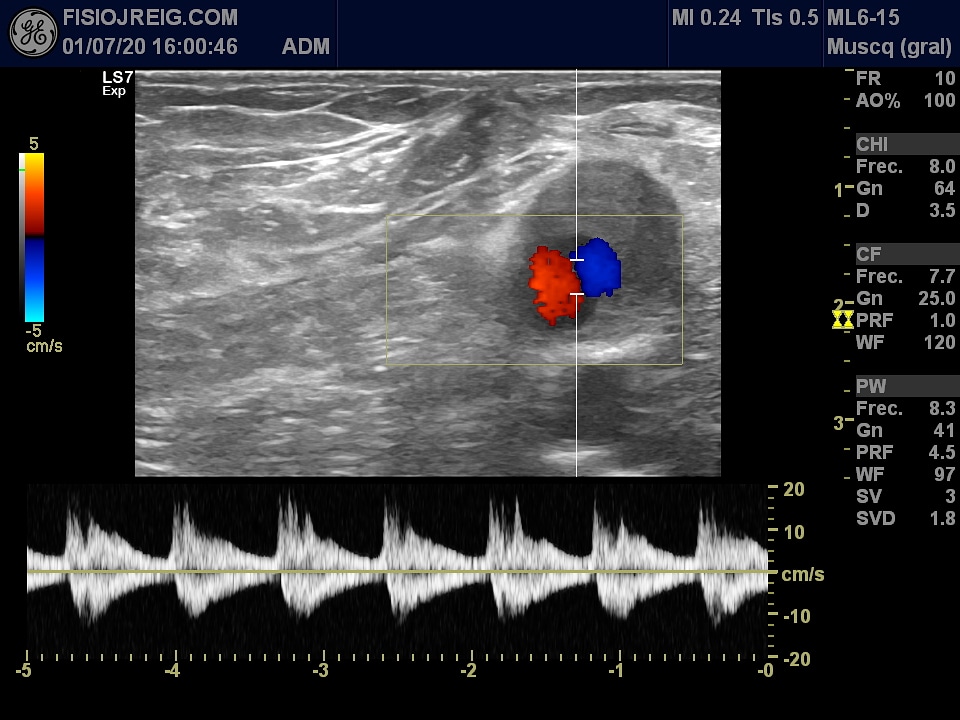

Nueva paciente con #trombosis venosa profunda poplítea. Derivamos a Urgencias Trabajamos con todas las medidas de protección para cuidaros y cuidarnos ! #Mitrabajomihobby PRIM Physio #Ecografia #LOGIQS7R3 fisiojreig

Jordi Reig Fisio (@jordireigfisio) 's Twitter Profile Photo

Aneurisma de la arteria femoral!! Cuanta información nos da la #ecografia a la hora de derivar a otros especialistas y saber lo que NO hay que tocar ! fisiojreig #formacion

Aneurisma de la arteria femoral!! Cuanta información nos da la #ecografia a la hora de derivar a otros especialistas y saber lo que NO hay que tocar ! <a href="/fisiojreig/">fisiojreig</a> #formacion